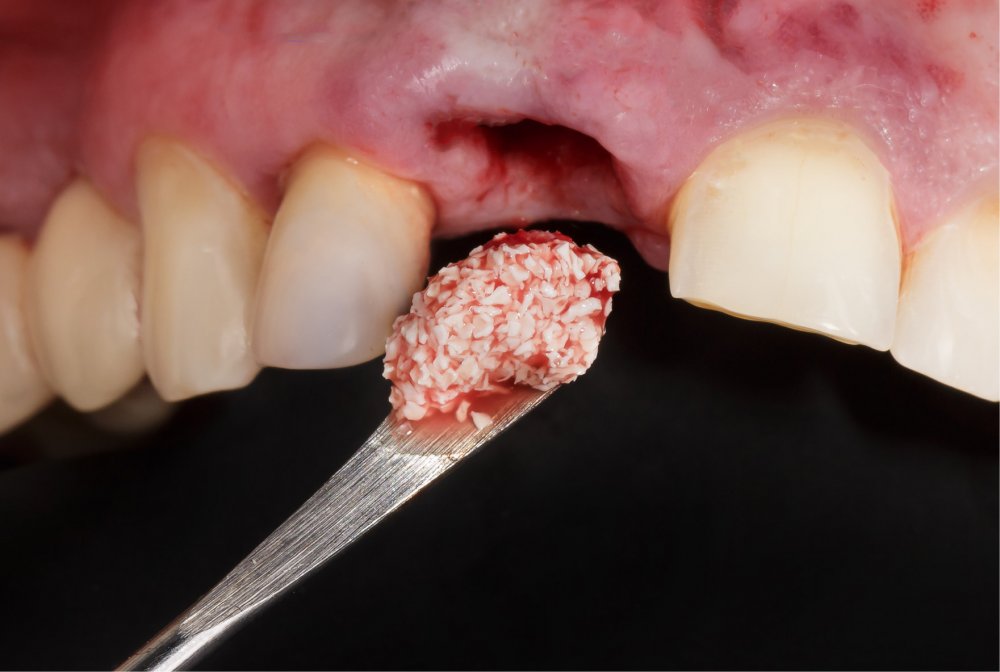

Bərpa texnikasının müəyyən edilməsi, sümüyün hansı bölgədə, hansı miqdarda itirilmiş olmasına bağlı olaraq müəyyənləşdirilir. Bərpa üçün tətbiq edilən sümük materialları pasiyentin öz donor bölgələrindən xüsusi metodlarla qazanılmış sümüklər, o cümlədən digər fərdlərdən alınmış və xüsusi qaydada hazırlanmış materiallar, heyvan mənşəli sümükəvəzləyici materiallar və sintetik materiallar olaraq ayrılır.

Bərpa zamanı yerinə görə bu materiallar ya ayrı-ayrılıqda, ya da kombinə olunmuş şəkildə tətbiq oluna bilir. Gündəlik təcrübədə həmçinin pasiyentdən götürülmüş qan nümunələrindən alınmış yüksək bərpaedici xassəyə malik materiallar (PRF) da uğurla tətbiq olunur. Sümükartırma metodlarının tətbiqi sayəsində, çənədə implantların yerləşdirilməsi üçün yetərsiz sümük həcmi olan bölgələrdə sümük miqdarı yetərli duruma gətirilir, uyğun boy və diametrə uyğun implantlar uğurla tətbiq olunur.